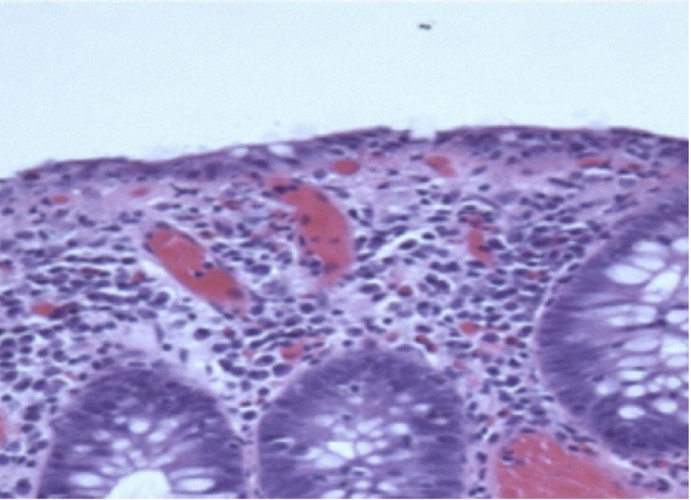

La CL presenta lesiones epiteliales superficiales leves. Presenta un infiltrado inflamatorio mononuclear mixto (plasmocitos, linfocitos) y escasos eosinófilos en la lámina propia; es poco frecuente la presencia de neutrófilos, en ausencia de un depósito de colágeno subepitelial. La CC presenta lesiones epiteliales superficiales moderadas a severas. Estas células epiteliales dañadas aparecen aplanadas e irregularmente orientadas. La banda de colágeno contiene capilares atrapados, glóbulos rojos y células inflamatorias (48) (Fig. 3).

Figura 2. Colitis linfocítica (HE × 100). Fuente: Engel PJH, Fiehn A-MK, Munck LK, Kristensson M. The subtypes of microscopic colitis from a pathologist’s perspective: past, present and future. Annals of Translational Medicine 20186:69. https://doi.org/10.21037/atm.2017.03.16